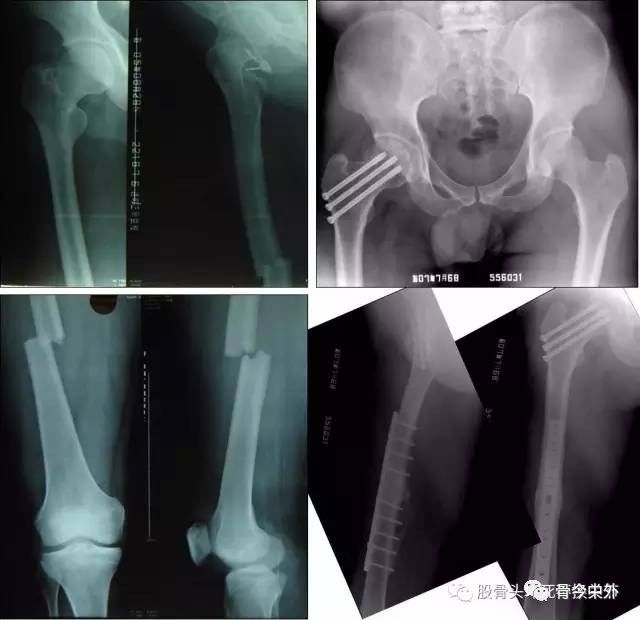

车祸伤、高处坠落伤等高能量损伤致股骨颈骨折的病例,可能还合并有其他部位的骨折,如:开放性骨折脱位,合并股骨头骨折,合并髋臼骨折,合并股骨干骨折,合并颅脑损伤等全身严重并发症。?

图14同侧股骨颈、干骨折分别内固定,愈合满意

图15?男性,30岁,同侧股骨颈、干、髁、髌骨骨折, 术后2个月各部位愈合顺利,肢体功能满意